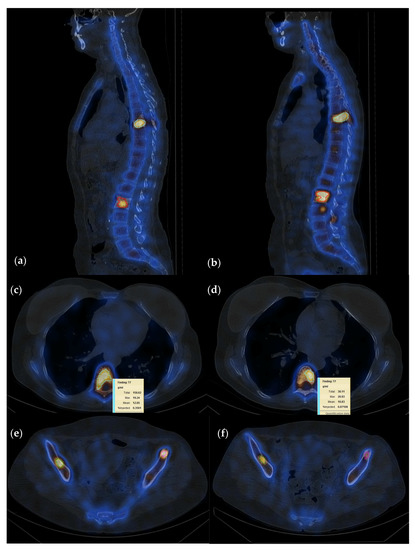

3.4. Interpretation of Quantitative SPECT-CT